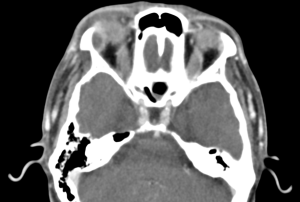

A contrast-enhanced computed tomography (CT) scan of the orbits will show enlargement of the lacrimal gland with a hypodensity and peripheral enhancement consistent with an abscess.[13][14] There may also be loculations of the abscess and fat stranding of the surrounding periorbita. On Magnetic Resonance Imaging (MRI) with diffusion-weighted imaging there may be restricted diffusion within the abscess.[14]